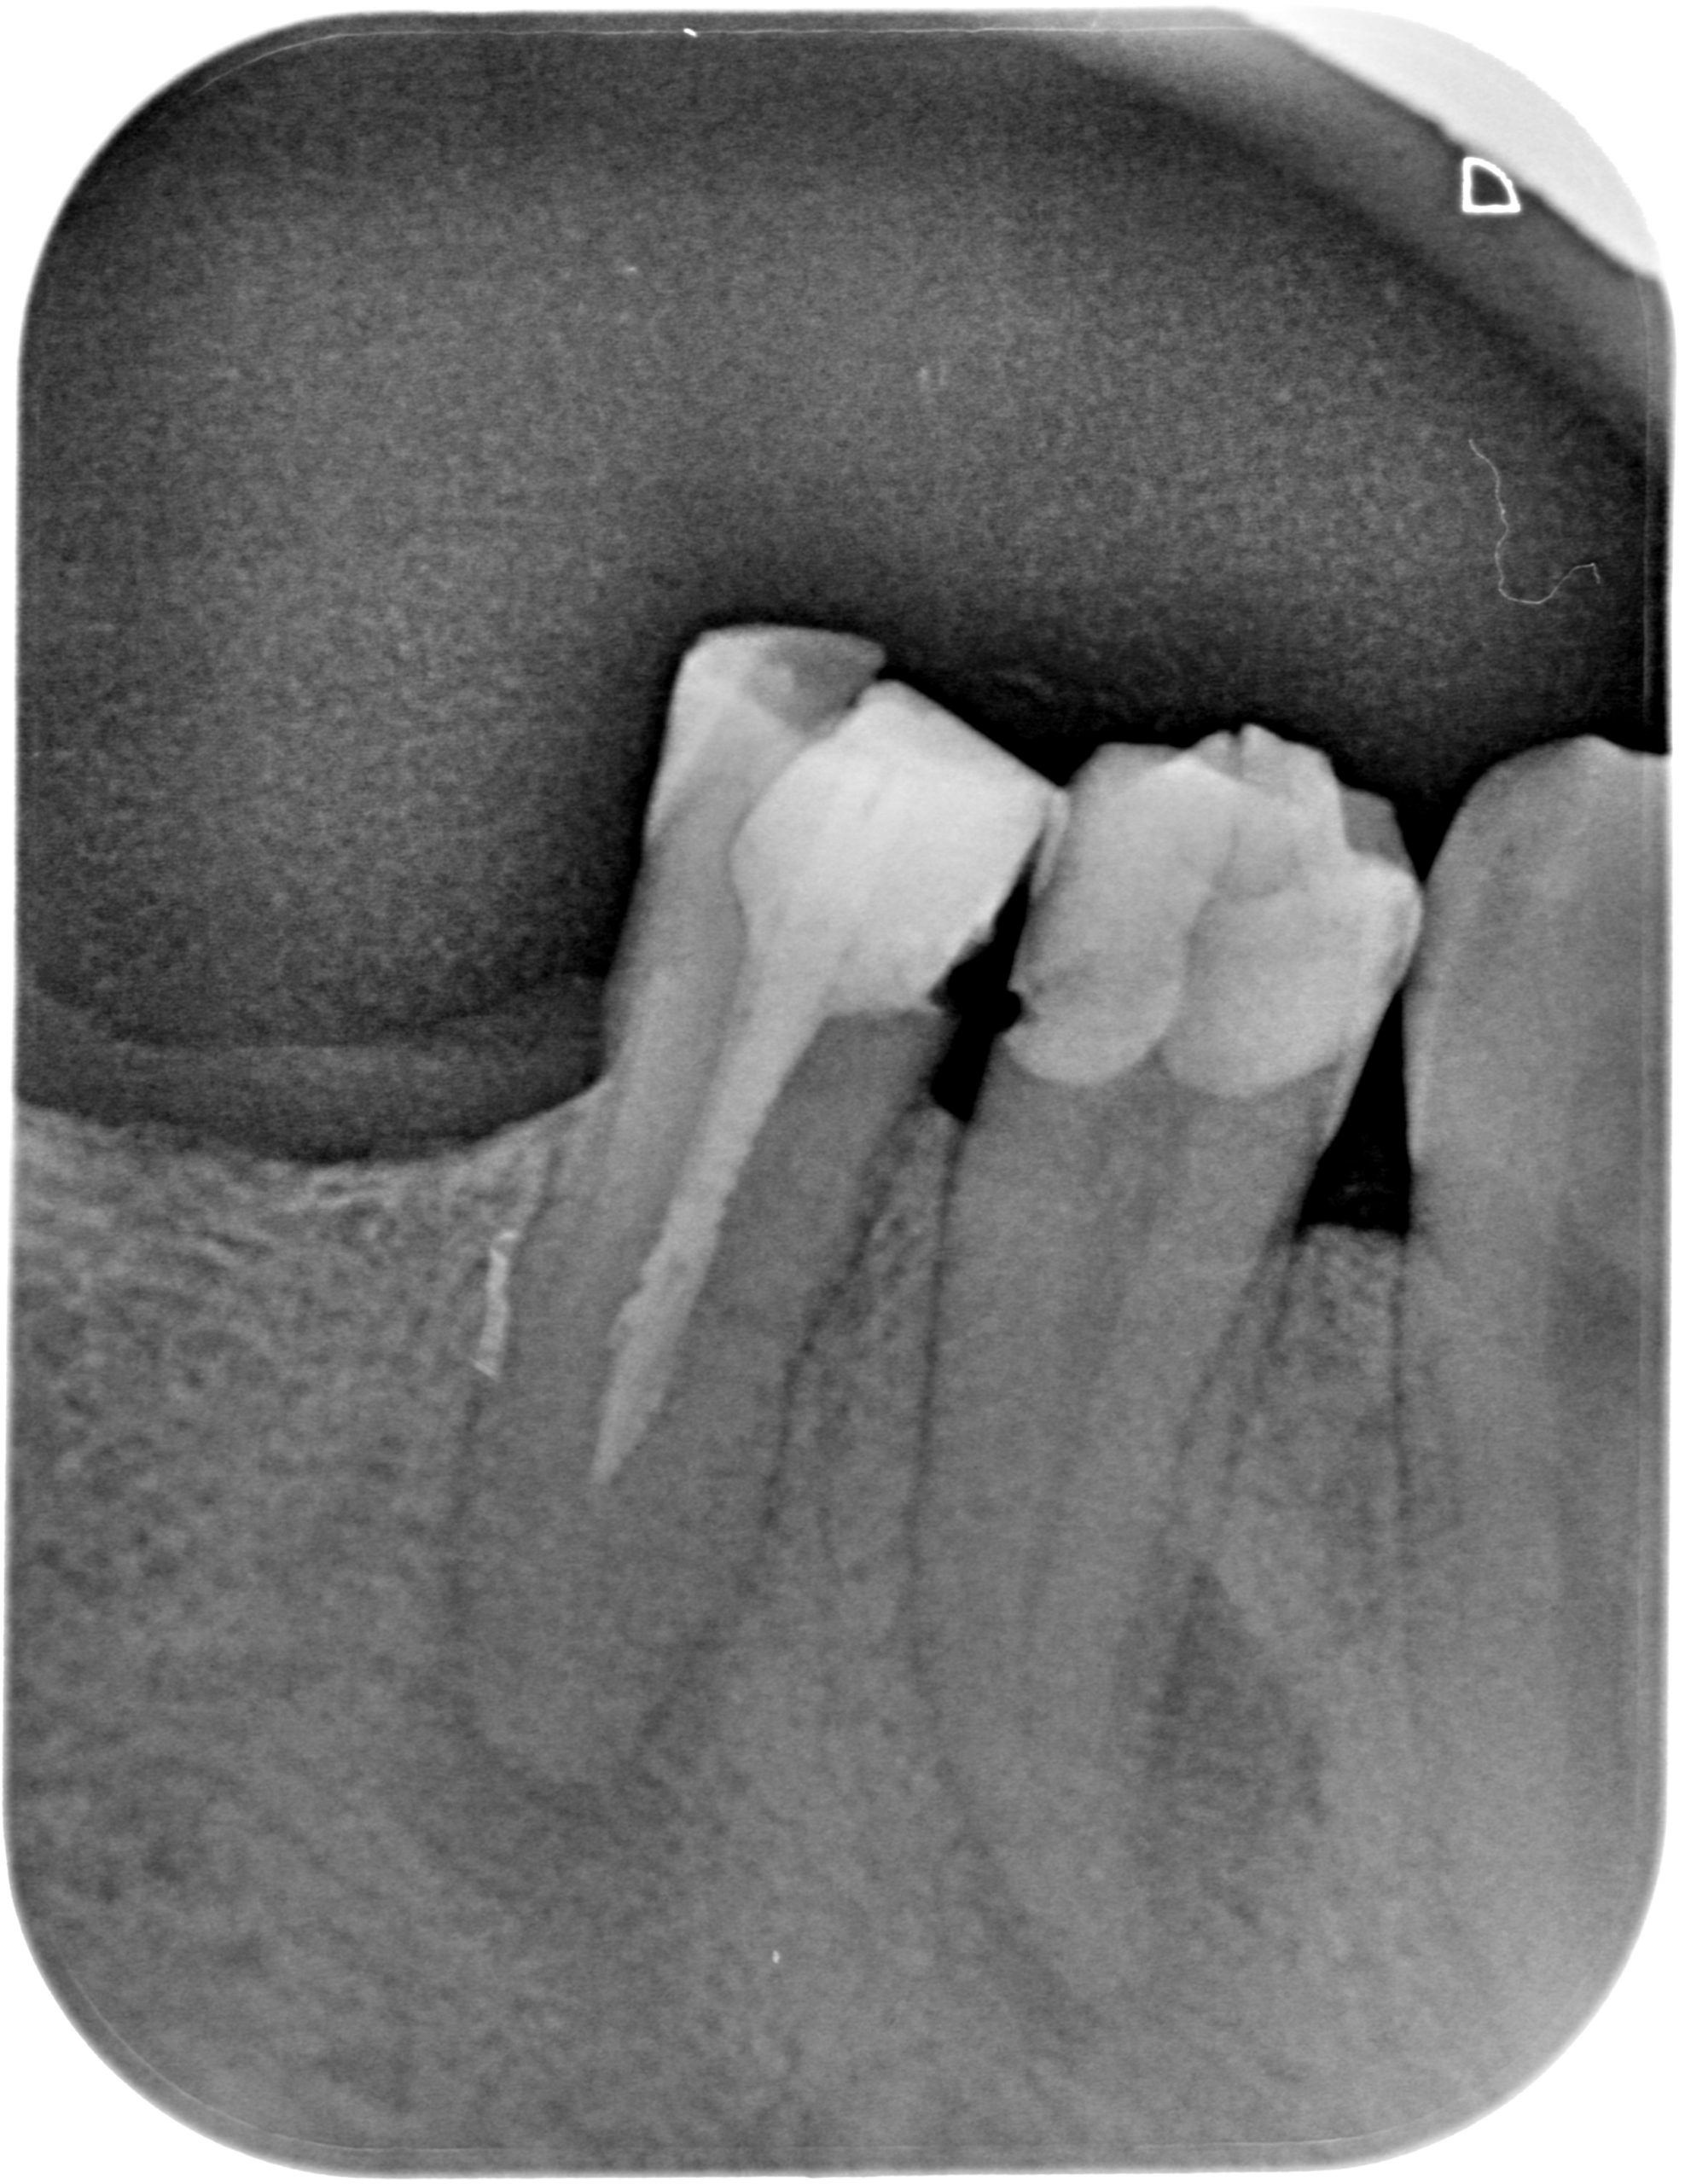

Caso clínico 2 – Tratamiento de conductos 4.4 + Retratamientos 4.5

RX Inicial:

Caso clínico 2 de endodoncia - RX inicial